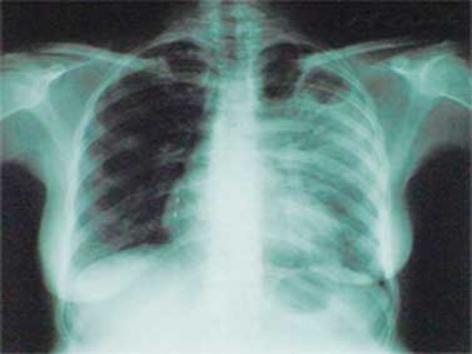

туберкулез

По ее словам, в прошлом году заболеваемость немного снизилась, однако в этом году возможно ухудшение. Причиной тому является большое количество переселенцев, которые продолжают прибывать в город. Манаенкова отметила, что сейчас на учете стоит три человека с открытой формой туберкулеза. В общей сложности, в городе 1380 больных и 300 из них имеют открытую форму заболевания. Манаенкова подчеркнула, что в сложившейся ситуации профилактика и выявление заболевания на ранней стадии развития становятся главными приоритетами.